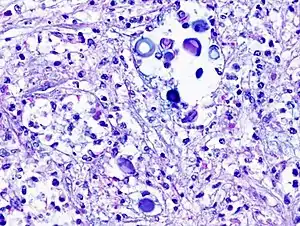

Biopsy

Mucicarmine stain: bright pink cryptococcosis capsule[33]

Field stain: thick cryptococcosis capsule

H&E stain: histiocytic penumonia_Alcian_blue-PAS.jpg.webp)